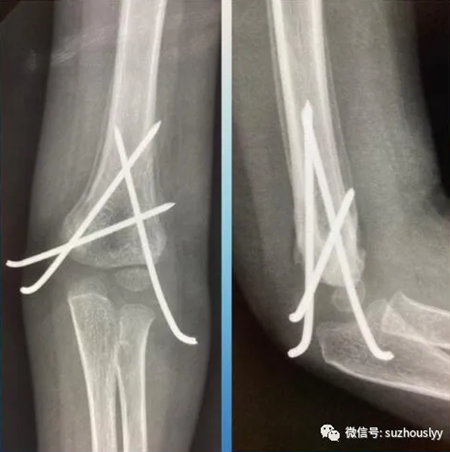

复查拍片子骨折完全复位、愈合

康复期间,患者间断复查,视频指导功能锻炼。近日复查见,骨折临床愈合,肘关节屈伸、前臂旋转功能锻炼良好。患儿家长非常满意,遂专程从灵璧赶往我院,送来锦旗,表示衷心的感谢,激动的心情溢于言表。

复查见功能良好,没有手术切口